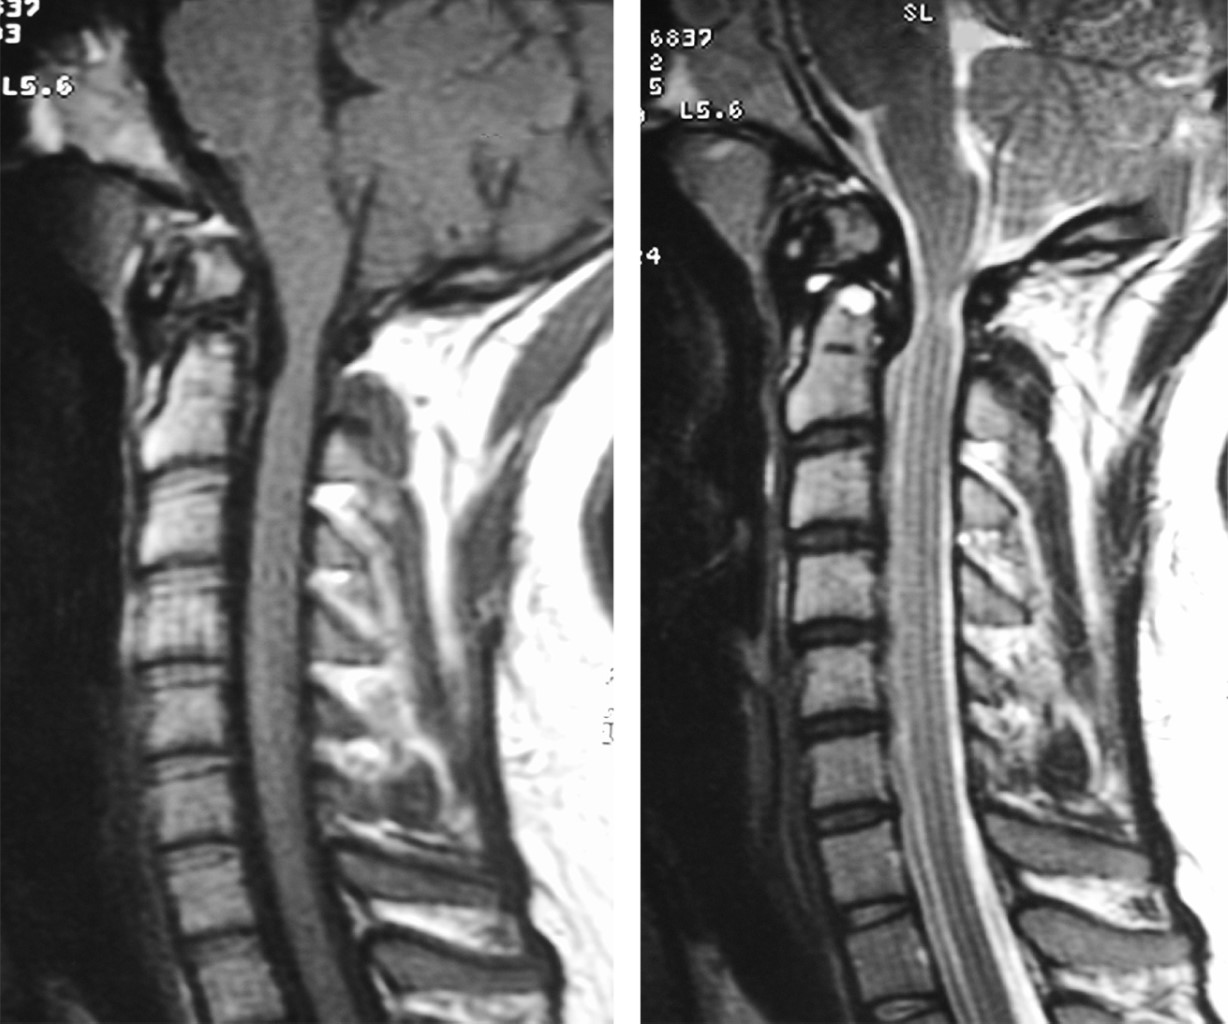

The os odontoideum is a variable oval or round ossicle with a smooth cortical border, which partially corresponds to the odontoid process, without having continuity with the rest of C2 bone. The multifactorial etiology causes instability and clinically translates into pain and compression data into neural structures. The treatment of choice is surgical and techniques have been developed that focus on preserving the stability of the segment. We present the case of a 23-year-old female patient, who begins to suffer at 8 years of age, refers to moderate to severe cervicalgia, which develops with paresthesias in the left hemisphere and later paresis of the left thoracic limb. Physical examination showed hypoaesthesia of the left hemisphere, as well as paresis of the left thoracic limb. Extension studies demonstrate chronic axonal lesion from C1 to C3, predominantly left, imaging studies showing axial instability and magnetic resonance bulbar compression. The patient receives surgical treatment consisting of posterior fixation C1-C2, evolving satisfactorily.

Figure 3